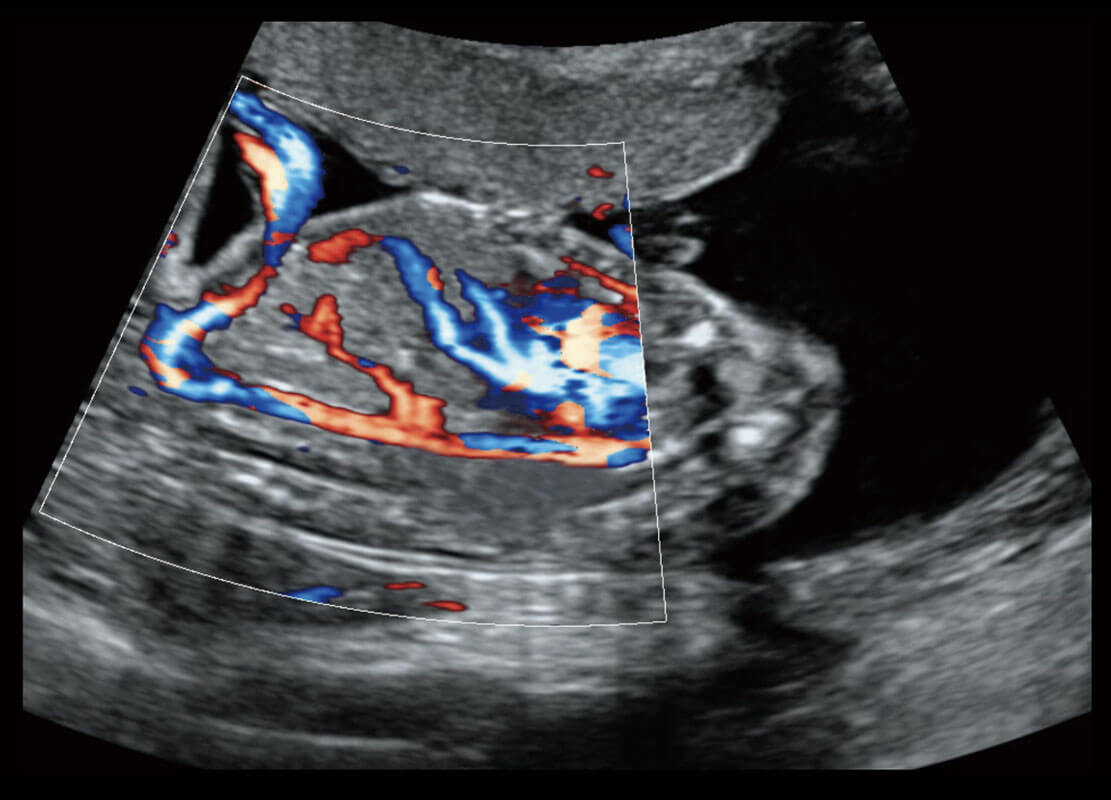

P60搭载宽频带线阵探头、宽景成像、弹性成像技术,为您提供乳腺应用方案。P60支持高频相控阵探头、线阵探头、腹部高频探头、腹部微凸探头等,丰富的探头群搭载敏感的彩色血流成像,适用于新生儿多种脏器检测要求,满足新生儿筛查需求。

乳腺癌显微血流

新生儿肝血管癌

新生儿心脏